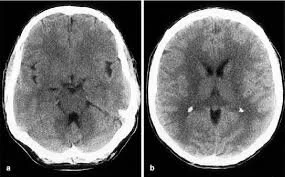

Collections of blood that form in the subdural space in the brain are common in patients 50 years and older, with head trauma the common cause. The subdural space is the area between the brain surface and the dura (covering) of the brain.